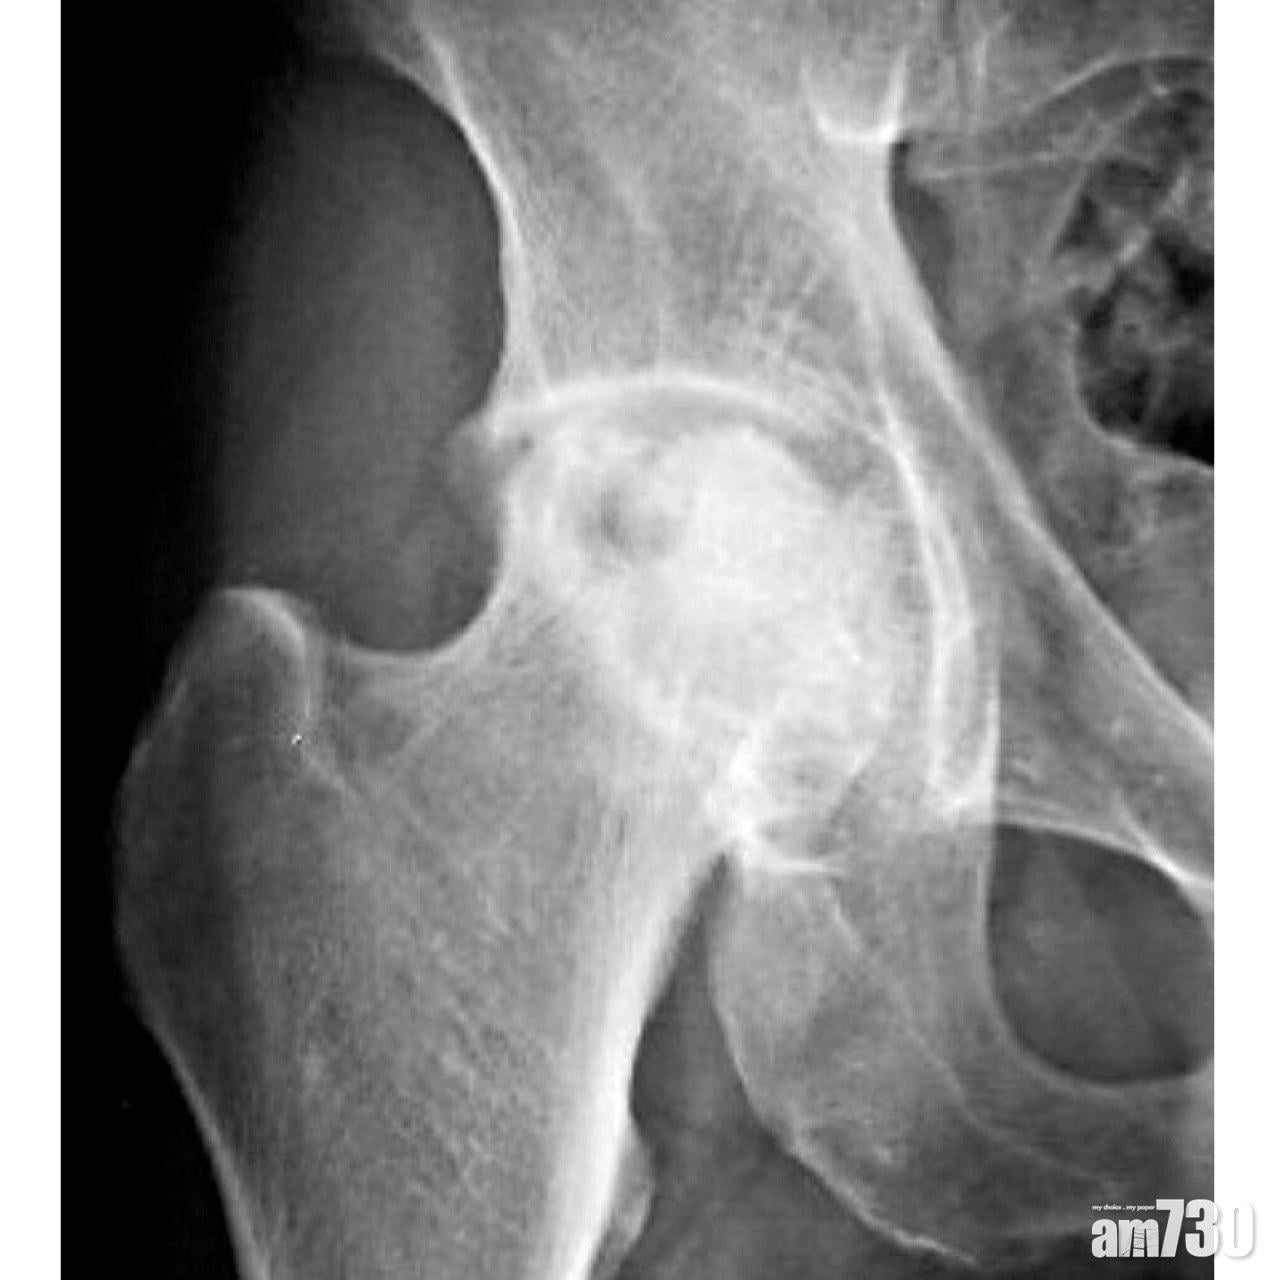

髖關節由股骨頭與骨盆的髖臼組成,但壞死的股骨頭會逐漸塌陷,令關節變得不平滑,軟骨在晝夜摩擦下加速耗損,最後更惡化成髖關節退化。患者起初只感到腹股溝隱隱作痛,到後期髖關節活動亦逐漸受限,難以再蹲下或翹腳。為減輕髖關節受力而產生痛楚,每當患者行走,輪到以患肢着地時,上身會習慣地傾向患側,來縮減身體重心的力矩,造成看似左搖右擺的步態。

單靠X光,在早期較難察覺股骨頭異常,需要照磁力共振或骨掃描來早日斷症。治療方面,透過非類固醇消炎藥、物理治療和使用拐杖,可紓緩髖關節痛。假如股骨頭尚未塌陷,患者可接受減壓及植骨手術,以防骨枯進一步惡化。但有不少患者在求診時,髖關節早已出現退化,惟有人工關節置換術,才可讓患者在無痛的路上重新出發。